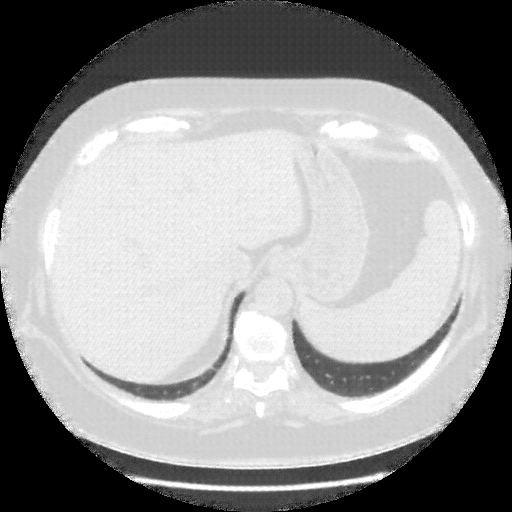

Original NATIVE CT scan (input)

Full window (WL 1023.5, WW 4095 β†’ Low βˆ’1024, High +3071)

Lung window (WL -600, WW 1500 β†’ Low βˆ’1350, High +150)

Mediastinum window (WL 40, WW 400 β†’ Low βˆ’160, High +240)